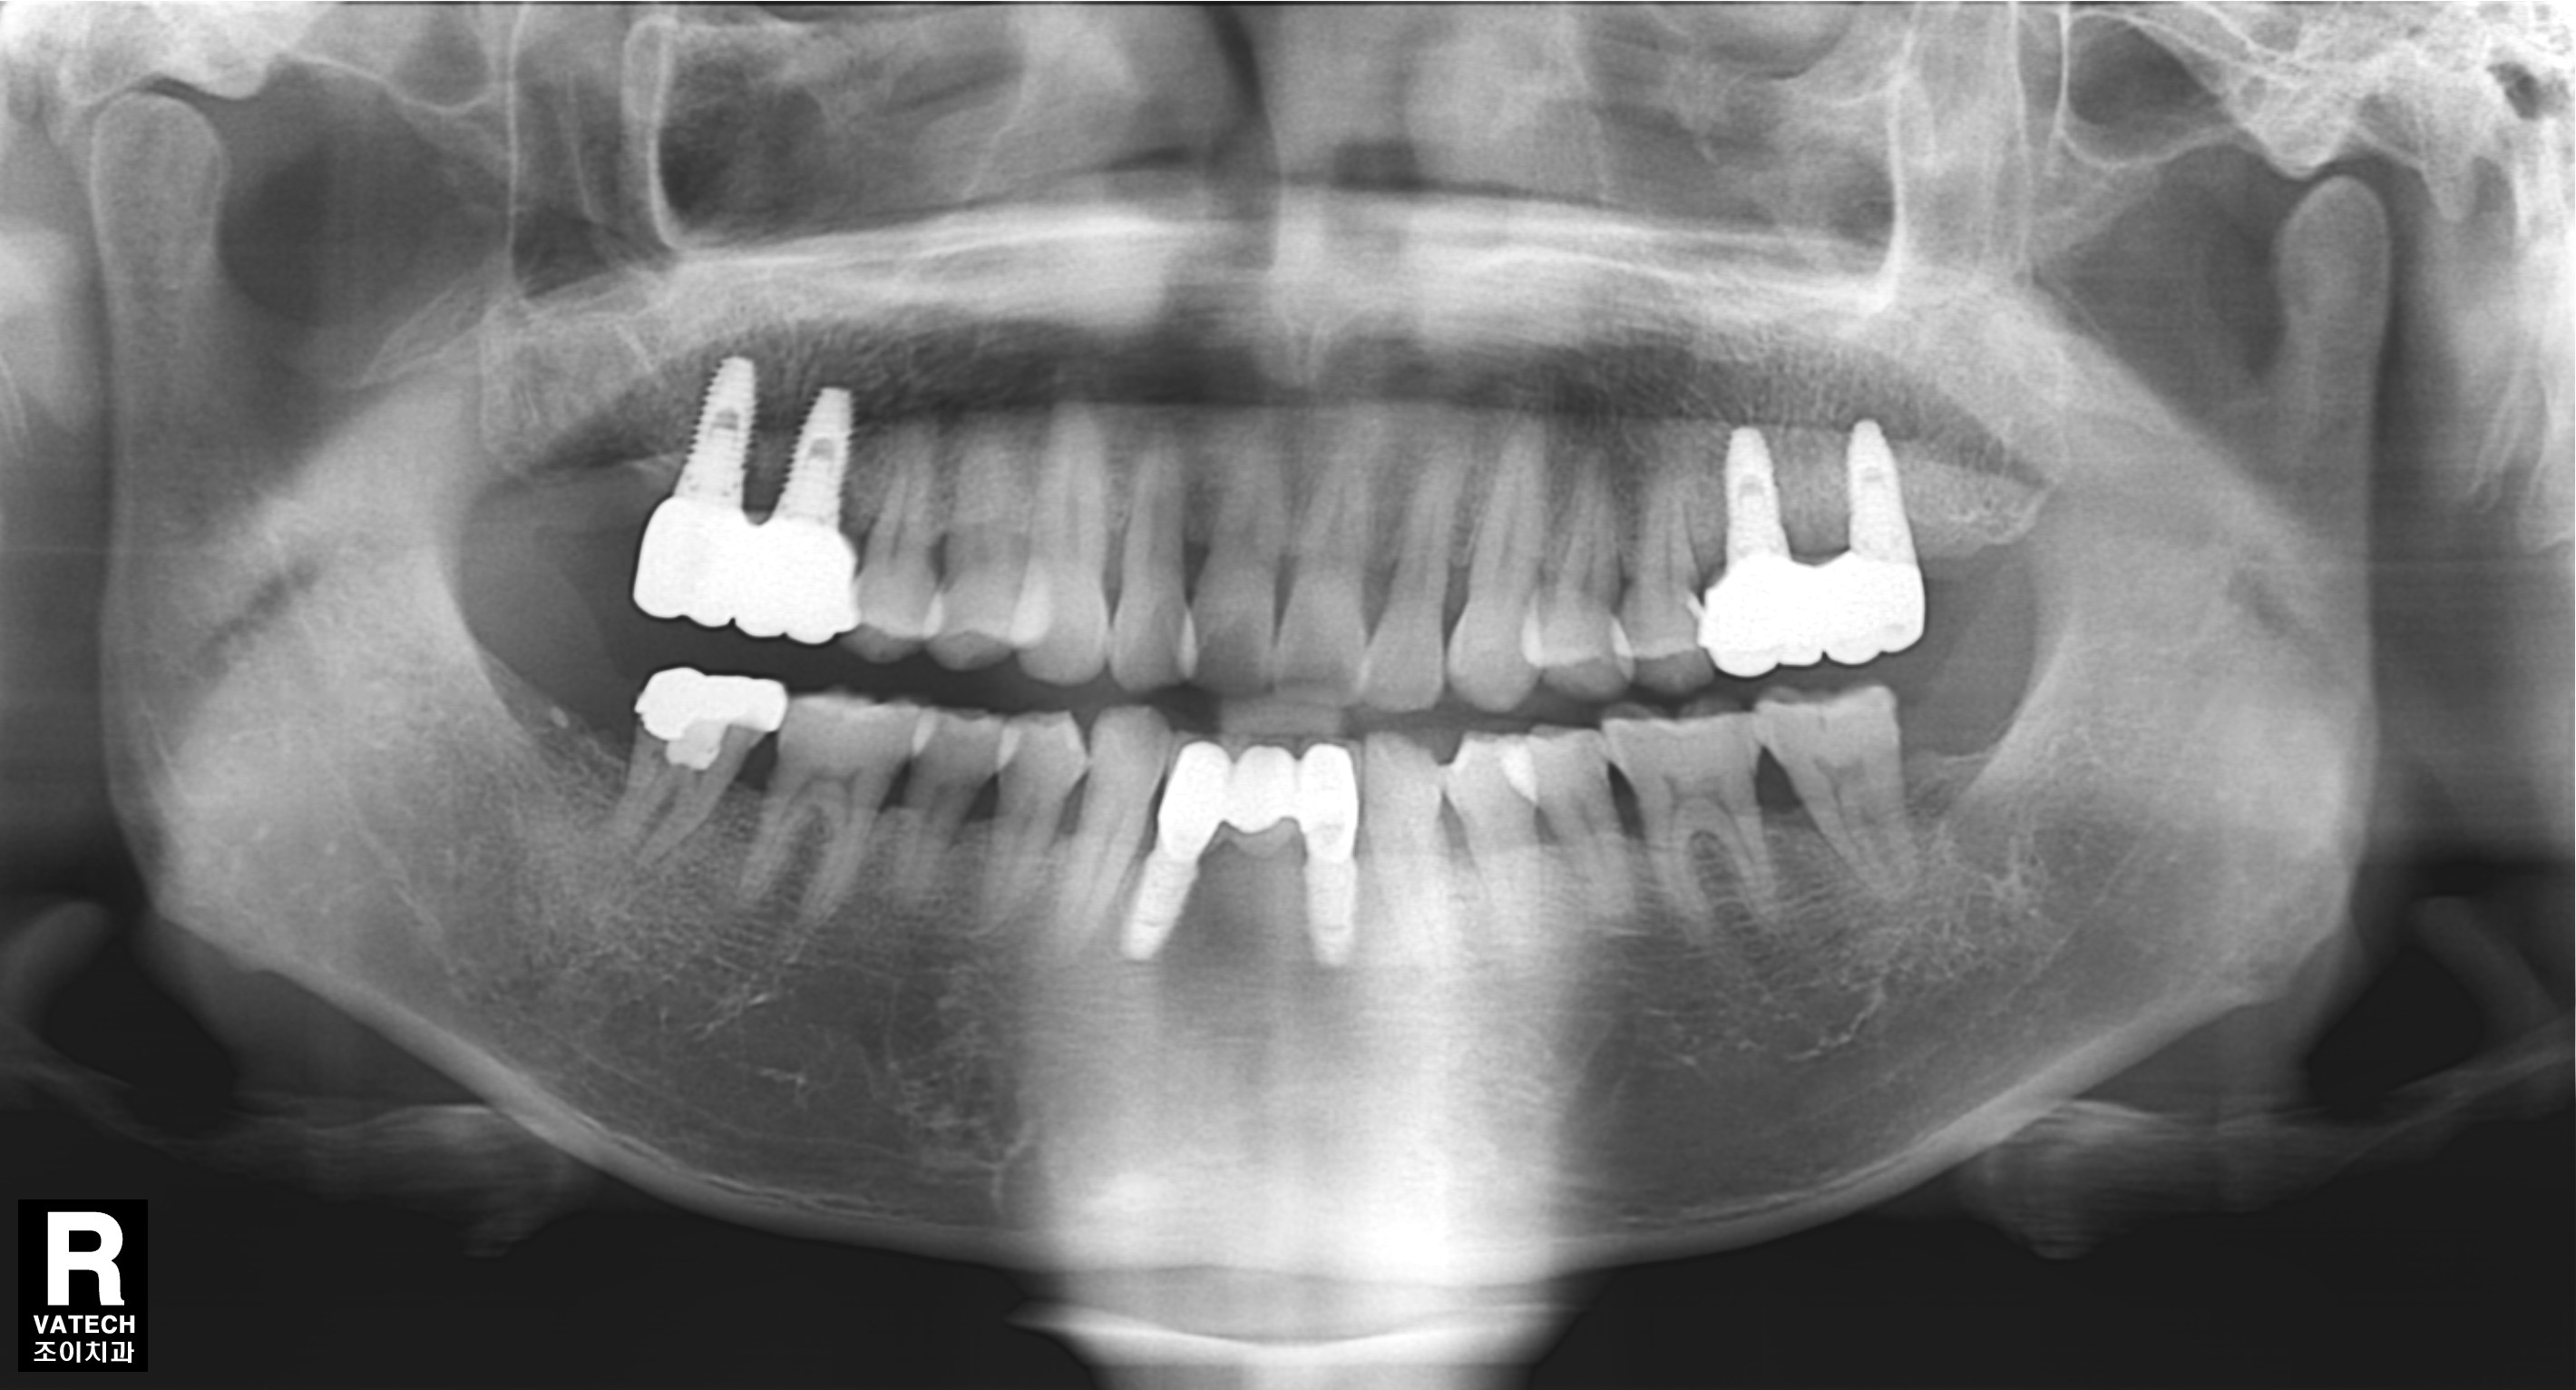

[임플란트] 제목 : 아래 앞니 임플란트

치주질환으로 발치 후 치료